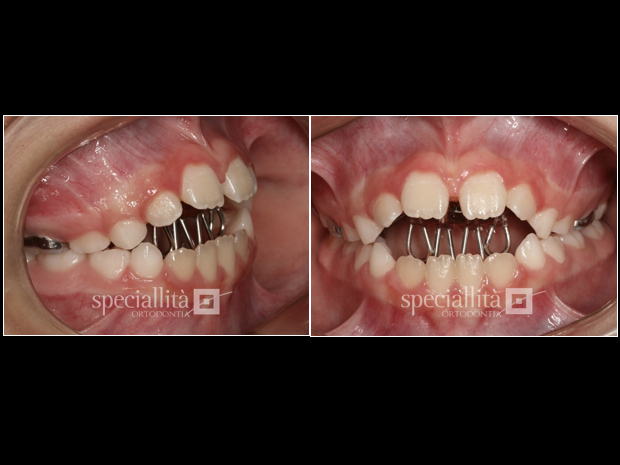

Utilização de Grade Lingual Fixa para impedir interposição lingual e permitir a correção da mordida aberta fisiologicamente, por meio de erupção dentária e crescimento alveolar na região anterior

Vista frontal da redução da mordida aberta anterior